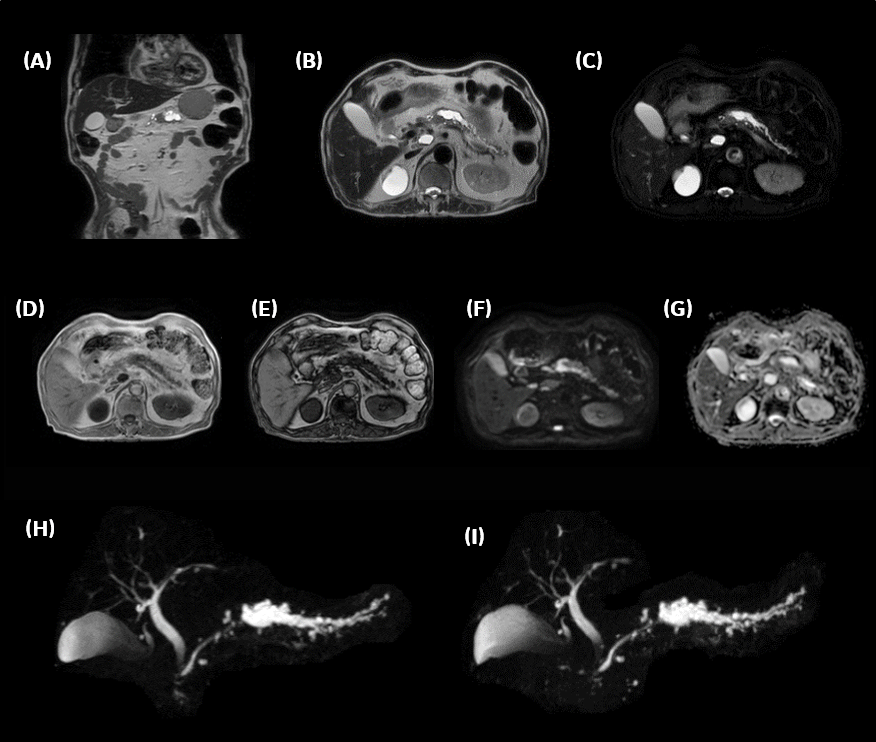

3D MRCPはスパース性の高い画像であり、圧縮センシングとの相性も良いといわれている。さらに高分解能に設定された条件下では、HyperSenseのfactorを上げやすいと感じている。参考例を図表4に示す。

MR29新機能を用いた臨床例。図表8に膵体部がん症例を供覧する。膵体部にDWI高信号を示し主膵管の拡張を来している。